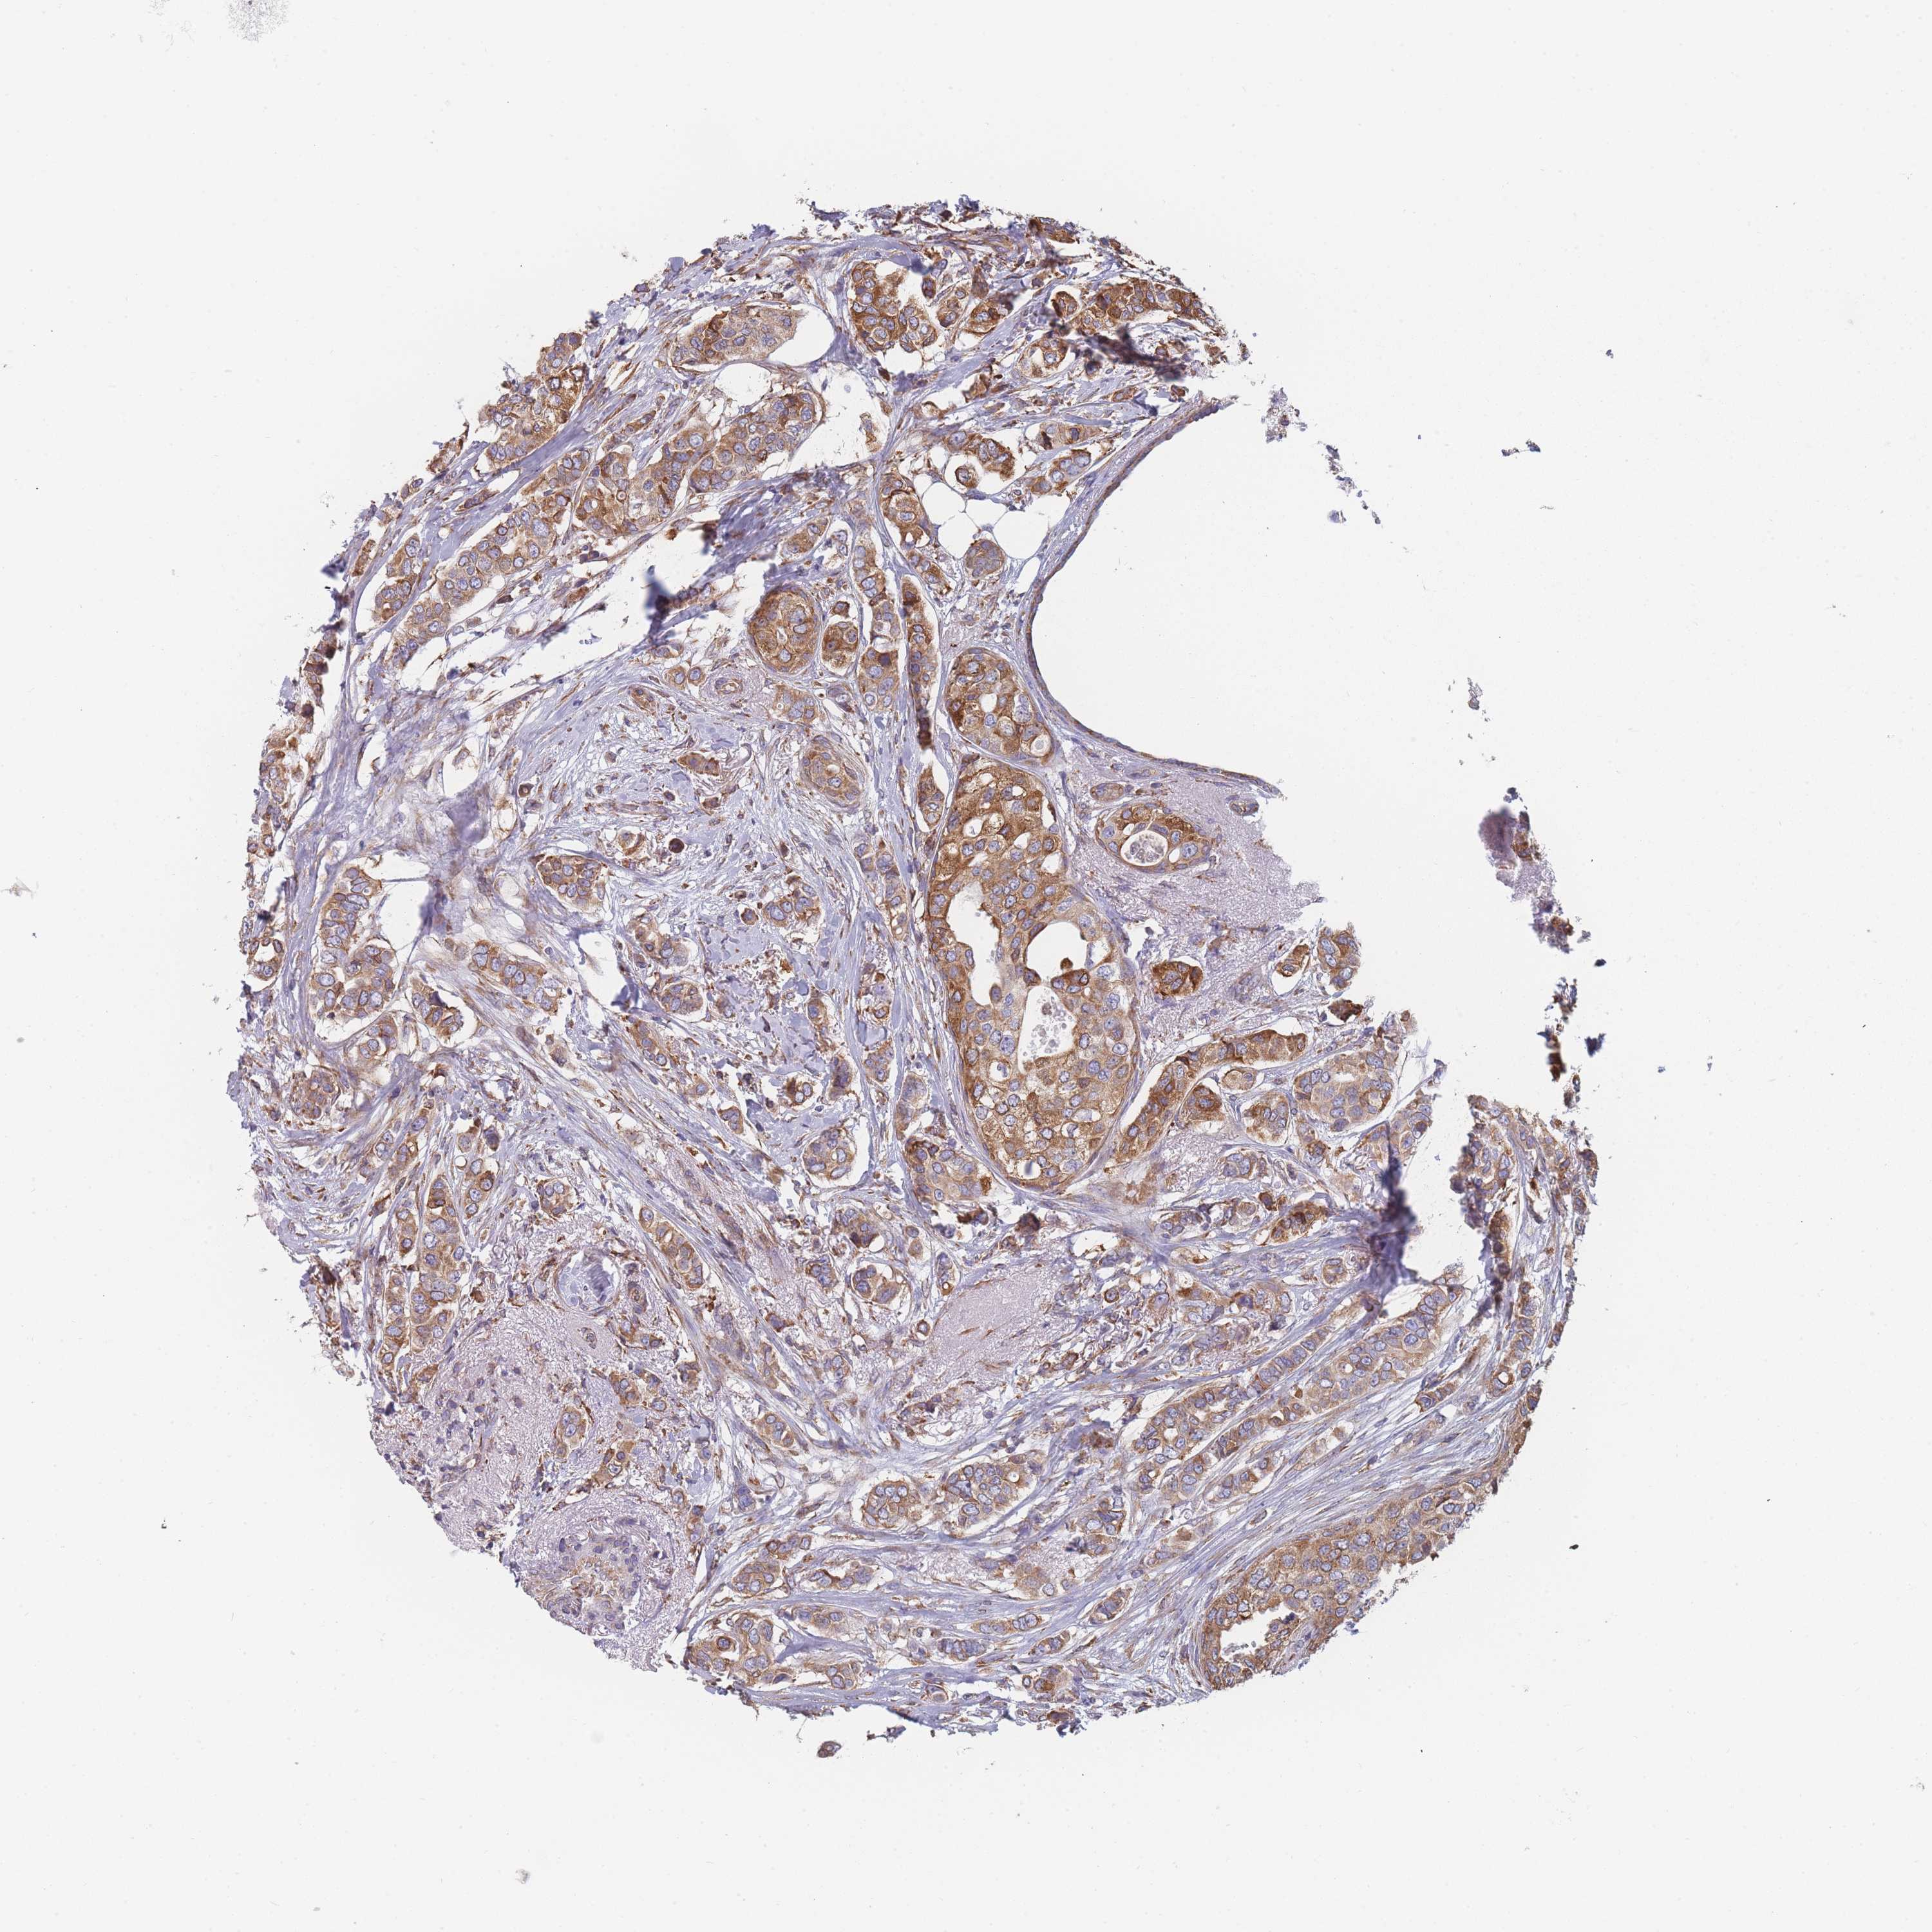

CANCER BREAST CANCER Show tissue menu

Breast cancer

Human cancer